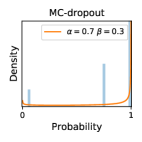

5.1 Distribution of Uncertainty Scores

Distribution of Uncertainty Scores Across Different Severity Levels As explained in Section 3, each uncertainty metric essentially defines an order/ranking among the data points. We conducted an analysis to better understand what data will be assigned high uncertainty under a particular uncertainty metric . Picking out the highest ranked data points (), we calculated the ratio of data points from each SL. Figure 4 summarizes the results as box plots for the Kaggle-DR and the Messidor-2 datasets; additional detailed statistics can be found in Table S.1 in the supplementary materials. From the plot and table, SL1 & SL2 examples account for a higher proportion among the top-ranked uncertain examples across the three ensemble methods. This finding matches our intuition that incipient disease examples (SL1 & SL2) are more likely to be considered uncertain by ensemble methods due to their ambiguity.

In contrast, the MC-dropout method showed the worst overall performance among the three, as it can be seen from the high ratios of SL0 examples among the uncertain negatives in Figure 4. The histograms in Figure 2 provides another perspective to look into the phenomenon, where a decent proportion of MC-dropout model’s predictions on SL0 inputs entailed low confidence (far from 0 or 1), which from another angle explained why MC-dropout was less specific in terms of lower FNP; many no-DR inputs (i.e. SL0) were erroneously assigned high uncertainty by MC-dropout models.

It is still an open question why the evaluated MC-dropout networks signaled relatively high uncertainty on SL0 & SL3 & SL4 data that are less likely to be ambiguous. We conjecture that much of the “uncertainty” indicated by disagreement among test-time dropout samples actually reflects the stochastic nature of dropout networks rather than the real decision uncertainty associated with the data. It is worth noting that the MC-dropout model we evaluated was not weak per se; they all achieved above Area Under Curve (AUC) scores on test sets. The weakness of individual test-time samples (which explains their low-confidence predictions on SL0 & SL3 & SL4) might have been hidden when they are aggregated into an ensemble—a well-known advantage of ensemble learning. Our results suggested that the uncertainty information given by implicit ensemble methods such as MC-dropout and TTA might not be as reliable as that from explicit ensemble approaches (e.g., stacking ensembles). Similar findings on MC-dropout can be found in some previous papers [1].